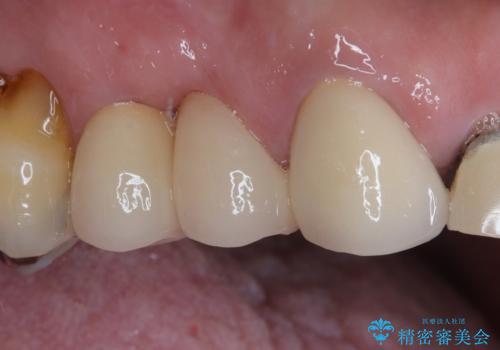

前歯のかぶせもののやり直し、根の治療も